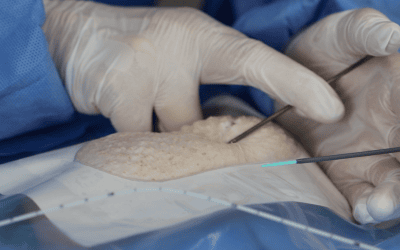

“Respecto a la retirada accidental, es importante asegurarse de la correcta fijación del DAV, usando adhesivos y en el mejor caso posible sistemas de anclaje subcutáneo”.